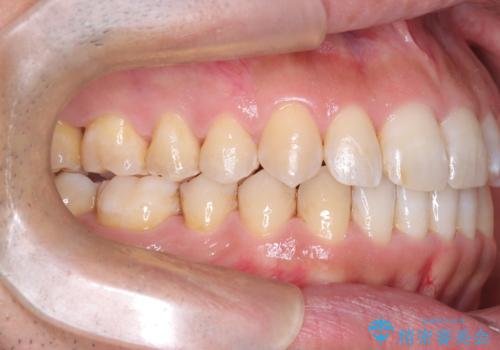

- 左上の八重歯を気にされて来院されました。精密な検査の結果、歯列全体を広げながら八重歯を奥へ移動させることで、美しい歯並びと機能的な咬み合わせが得られると診断。患者様のご希望に合わせ、透明で目立ちにくい**インビザライン(マウスピース矯正)**による治療計画を立案しました。抜歯を避け、歯を少しずつ遠心(奥)へ移動させることで、歯が並ぶスペースを確保し、叢生(歯のデコボコ)を改善します。

今回の矯正治療では、透明なマウスピース型の装置インビザラインを使用しました。この装置は目立ちにくく、取り外しが可能なため、食事や歯磨きも普段通りに行えます。遠心移動という方法で奥歯を後方に動かし、前歯を並べるためのスペースを確保。これにより、抜歯することなく、左上の八重歯を含む叢生を効果的に改善し、整った美しい歯並びと良好な咬み合わせを獲得していただけました。